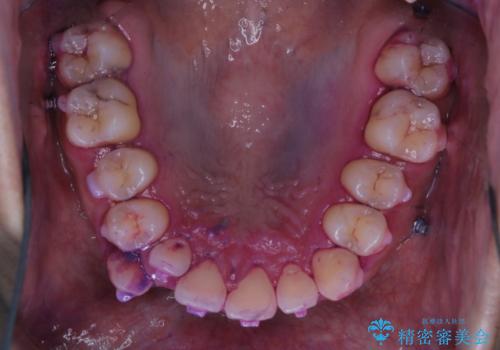

しかし、プラークは歯の色と似ているため、見ただけでは付着しているかどうかがハッキリとは分かりません。

染め出し液を使ってプラークを染め出すことにより、普段の歯みがきで磨き残している場所を目で確かめることができます。

日々の歯磨きを上達するには、まずどこが磨けていないか認識することが大切です。